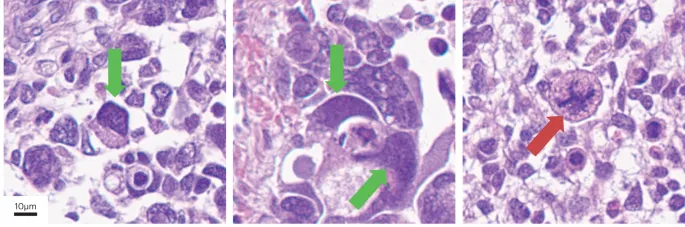

- Dysgerminoma: Most common malignant GCT; ↑LDH; radiosensitive. "Fried egg" cells.

⭐ Dysgerminoma is the ovarian counterpart of testicular seminoma and is highly radiosensitive.

- Dysgerminoma: Most common malignant GCT; radiosensitive; ↑LDH, ↑hCG.